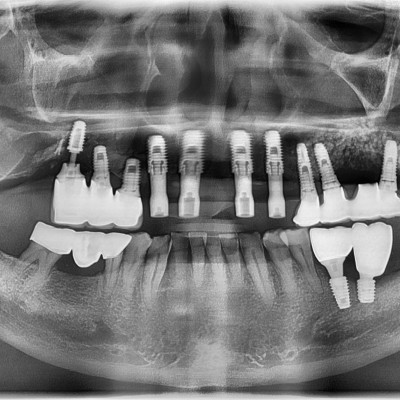

임플란트 재수술 #14.15.16.17 타원 임플란트 제거 후 임플란트 식립+ 치조골 이식술 시행하였습니다.

작성자 이턱이 작성일 01-27 조회 111